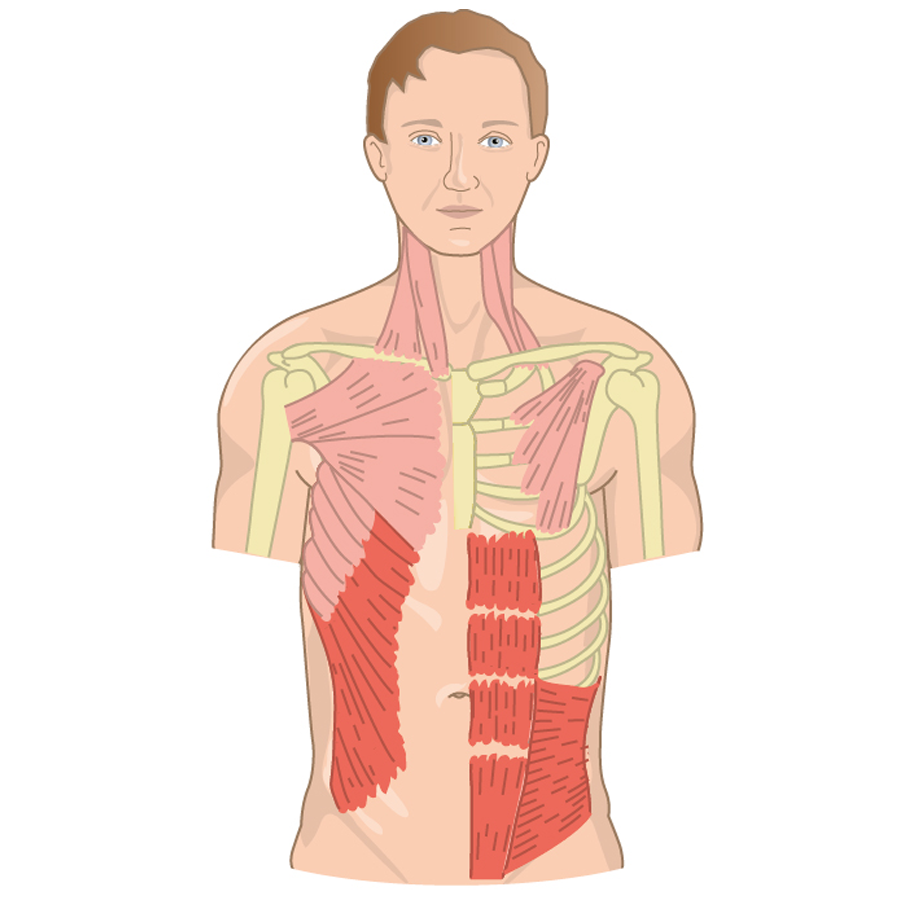

Herzlich willkommen! Ich bin Ihre Expertin für medizinische Illustrationen und kreative Kinderbuch-Illustrationen. Mit einem Auge für wissenschaftliche Genauigkeit und einer Liebe zur Gestaltung kindgerechter Erzählwelten schaffe ich Bilder, die informieren und begeistern. Entdecken Sie mein Portfolio und lassen Sie sich von meiner Arbeit überzeugen!